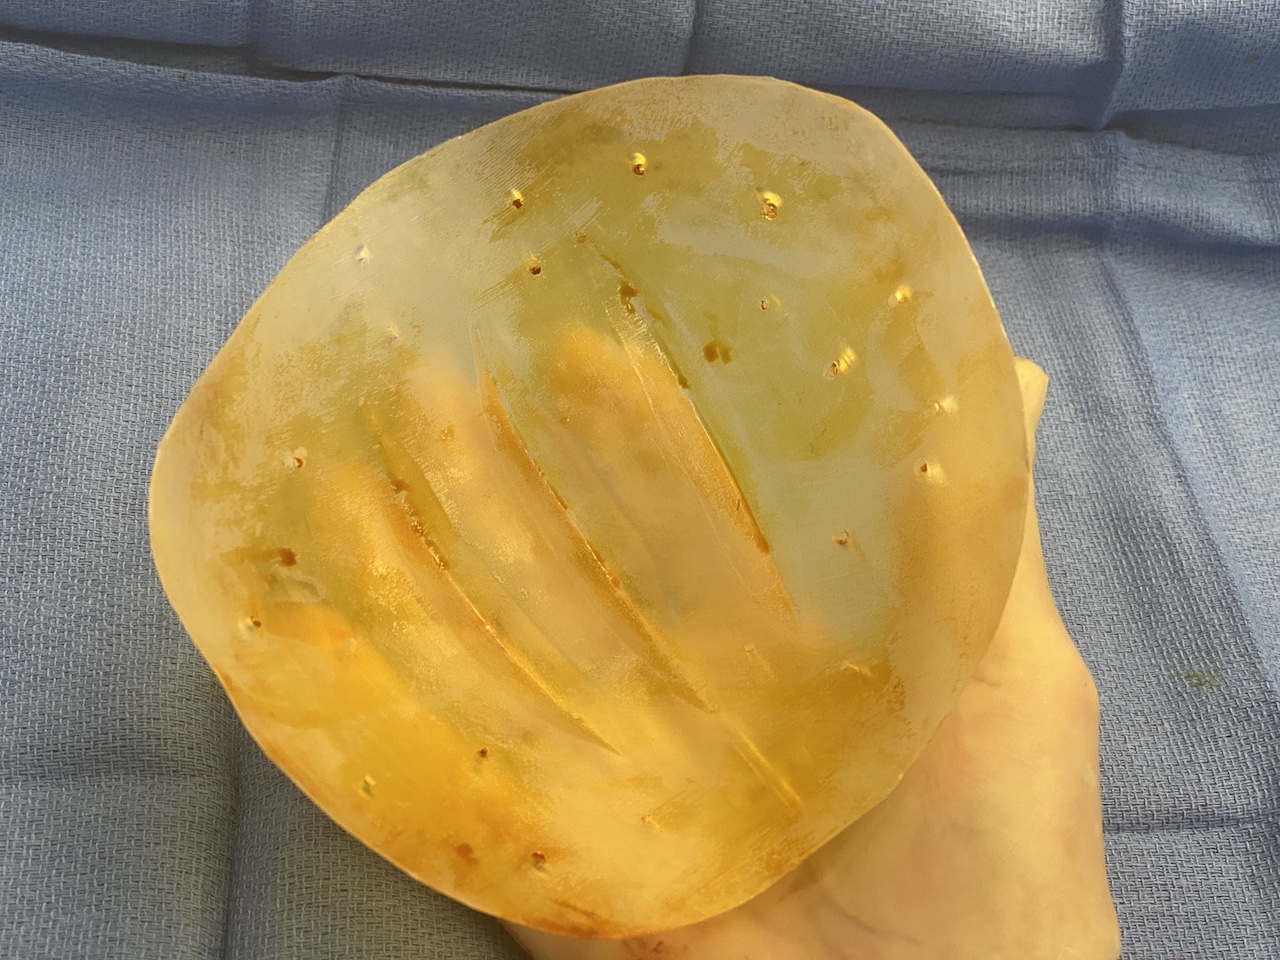

Desire for major head reshaping with a taler and wider head shape.

Placement of large two piece custom skull implant through a sagittal scalp incision.

Desire for major head reshaping with a taler and wider head shape.

Placement of large two piece custom skull implant through a sagittal scalp incision.